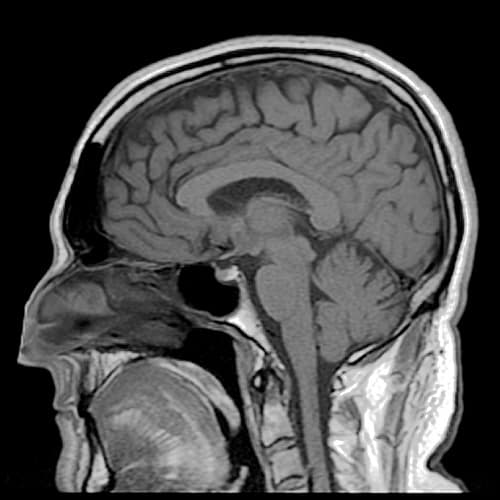

Longtemps négligées car considérées comme intervenant à l’ultime stade du cancer, les métastases cérébrales font l’objet jusqu’à dimanche à Marseille, d’une conférence internationale pour mieux cerner leur origine et définir un traitement plus adapté.

Premier objectif: améliorer le traitement, compliqué par le fait que le cerveau, sorte de sanctuaire, est “un peu déconnecté du reste de l’organisme par une barrière protectrice dite hémato-encéphalique”, relève Anthony Gonçalves, oncologue médical à l’institut marseillais Paoli-Calmettes.

“Dans le traitement des métastases cérébrales, l’existence de cette barrière peut gêner l’arrivée des médicaments à l’intérieur du cerveau”, poursuit-il.

Découvertes le plus souvent fortuitement à l’occasion d’examens radiologiques, les lésions cérébrales peuvent se manifester par des symptômes tels que des céphalées, des crises d’épilepsie, des hallucinations et des troubles cognitifs.